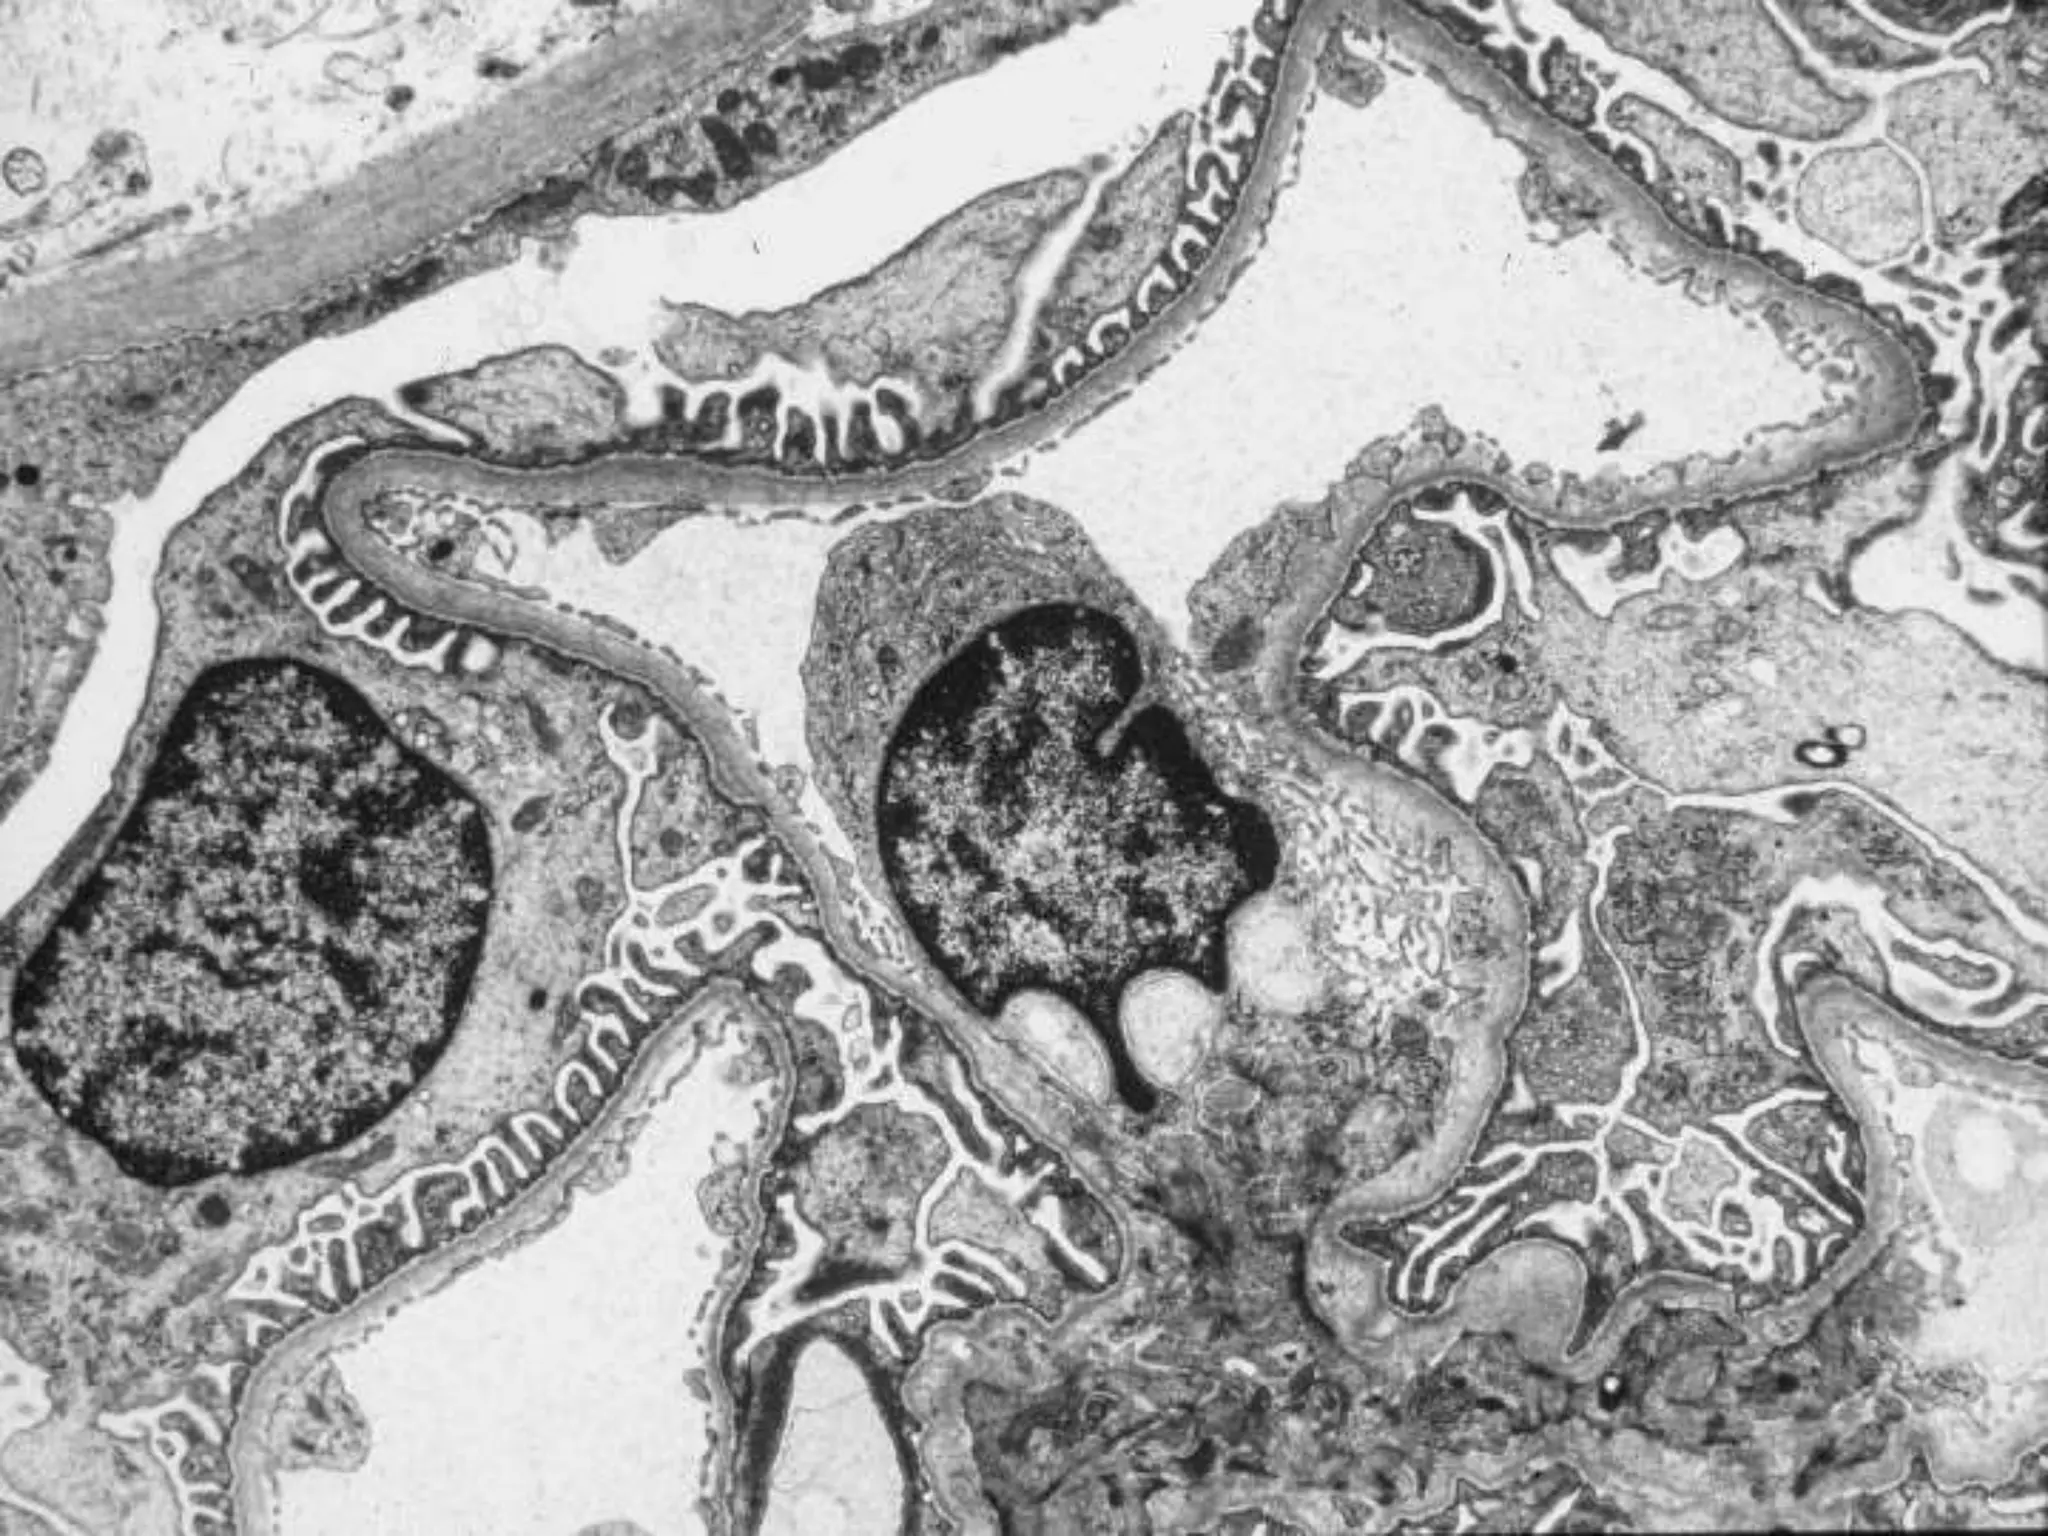

Review of the biopsy specimen

• Glomerulus: Diffuse/focal. Segmental/global.

• Endothelium, glomerular basement

membrane, podocyte, mesangium (cells and

matrix), urinary space, Bowman’s capsule.

Review of thebiopsy specimen • Glomerulus: Diffuse/focal. Segmental/global. • Endothelium, glomerular basement membrane, podocyte, mesangium (cells and matrix), urinary space, Bowman’s capsule. • Interstitium: Tubules, casts, fibrosis, inflammatory infiltrate, arterioles • Light, immunofluorescence, and electron microscopy constitute a full biopsy